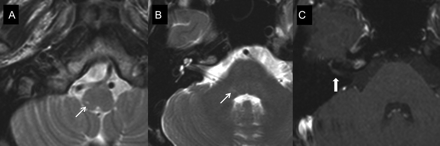

教学神经图片:MRI Ramsay-Hunt三叉神经带状疱疹后综合症

Donghoon哦,Seong-Ho公园